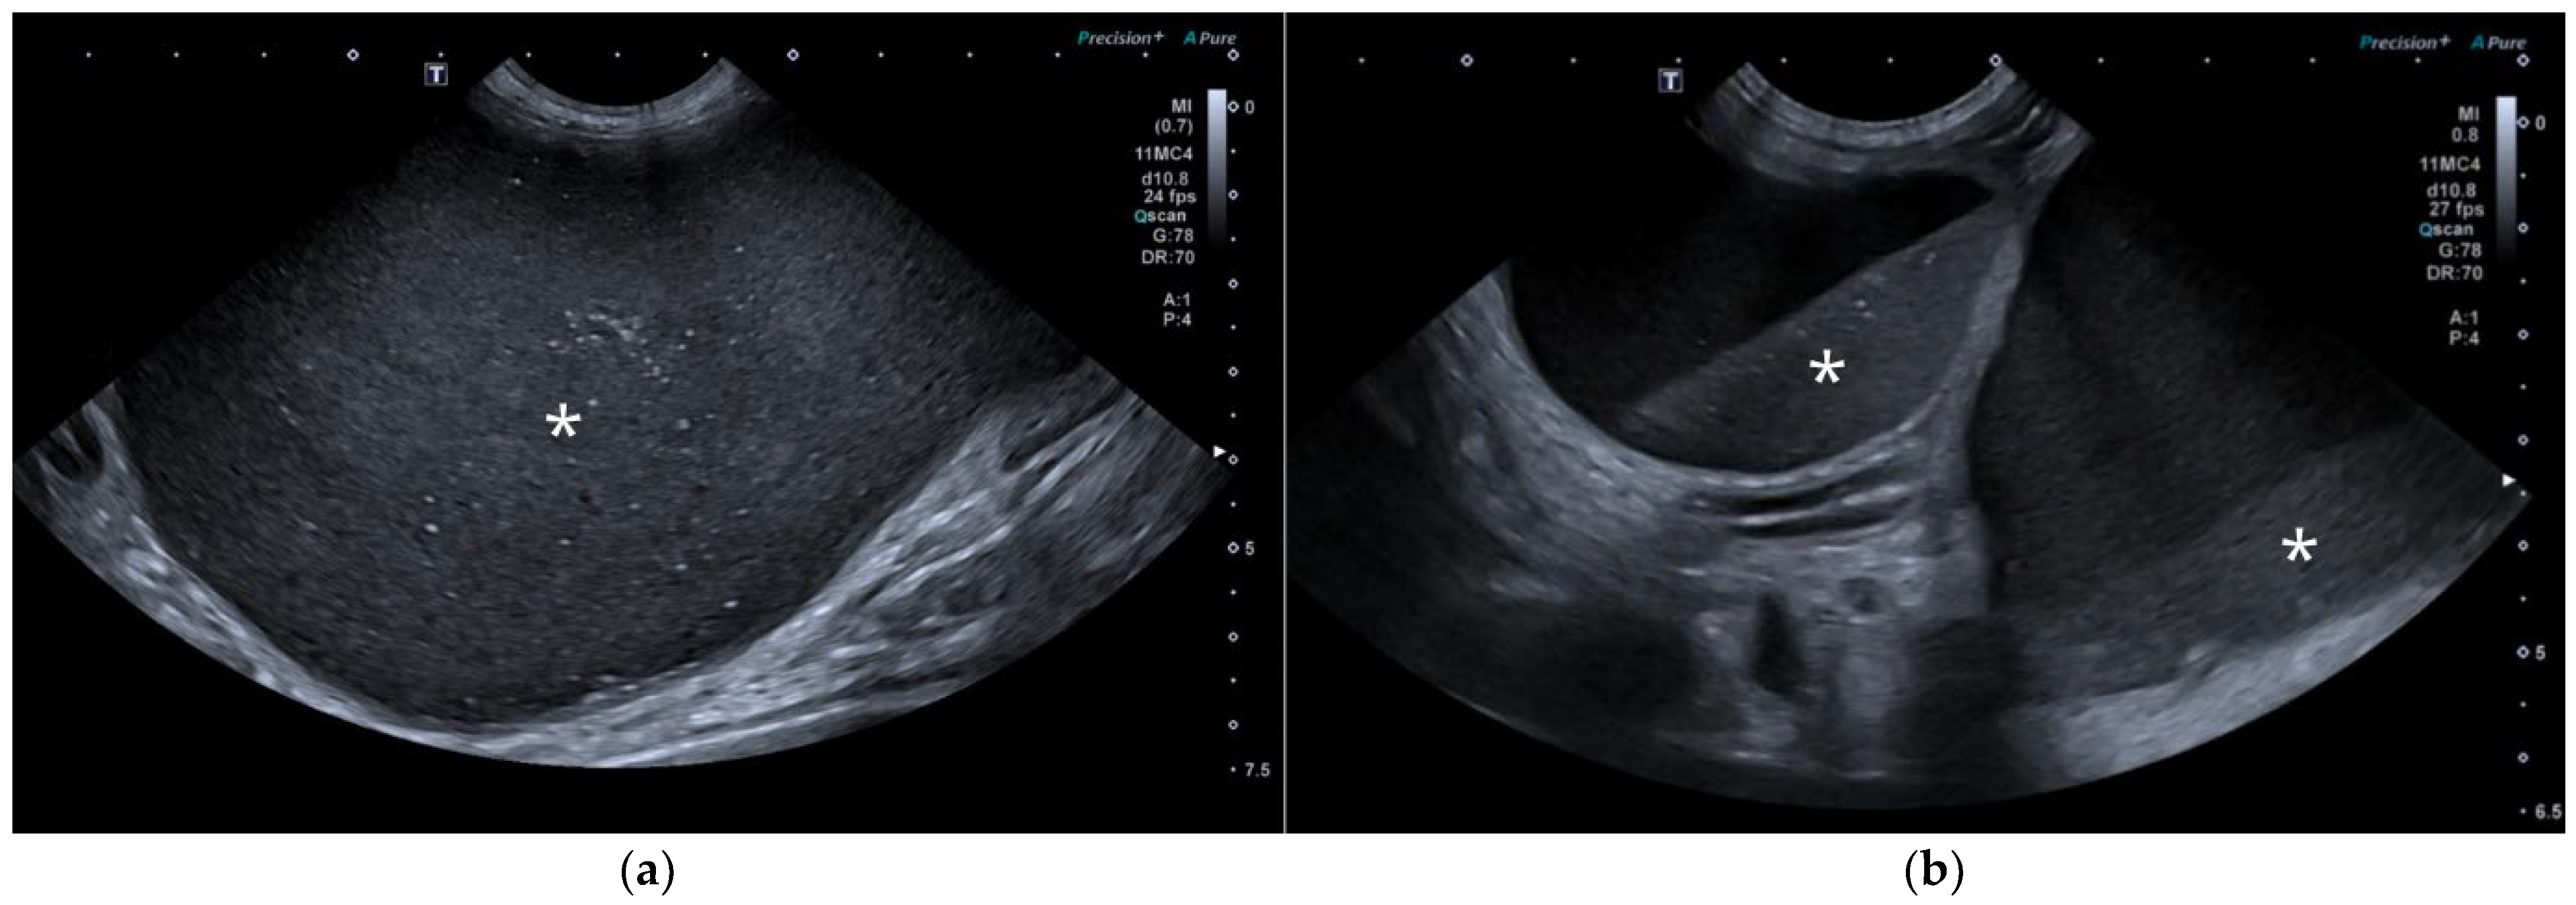

AUS in all three dogs revealed a fluid-filled cavitary structure originating in the caudal peritoneum between the colon and urinary bladder and extending cranially through the mid-abdomen, causing a mass effect. In cases 1 and 2, the lesion continued bilaterally as paired, thin tubular extensions coursing caudally through the inguinal rings adjacent to each testis (Figure 1a). In case 1, a focal mural narrowing resembling a uterine cervix was noted caudally (Figure 1b). The wall was thin and smooth in case 1, while in case 2 it was irregular, especially in its caudal aspect (Figure 2a,b). No information was available regarding the course of the UM horns or wall appearance for case 3. The luminal content consisted of echogenic, inhomogeneous fluid in all cases (Figure 3a); in case 2, sedimentation created fluid–fluid levels (Figure 3b).

Figure 2. AUS of case 2: (a) Longitudinal view of the caudal UM, showing irregular wall margins (arrows), intraluminal inhomogeneous fluid, and free echogenic peritoneal fluid (arrowheads); (b) Detailed view of the UM wall demonstrating luminal irregular margins (arrows).

Figure 3. (a) AUS of case 1; transverse view of the most dilated UM segment containing inhomogeneous echogenic fluid; (b) AUS of case 2; oblique view showing two sections of the UM containing a moderate volume of sedimented material (asterisks), creating marked fluid–fluid levels.